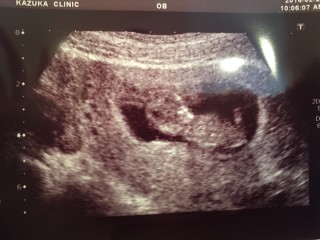

写真:11w0d:ちかさん

11w0d 45.9mm

CLR43.4。

この日は寝てたのか、ほとんど動かず大人しかったです。

4Dエコーも見ましたがちゃんと人間の形をしててびっくり。

お顔を手で隠している仕草が愛らしかったなぁ^^